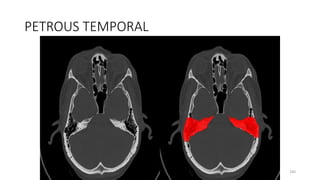

PETROUS TEMPORAL